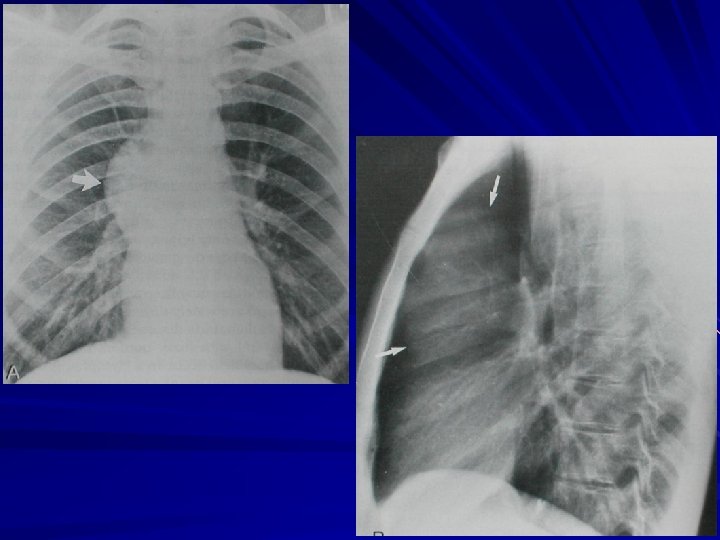

Yan dekübitus grafisi En hassas projeksiyon 25 ml sıvı görülebilir. Serbest sıvı yan göğüs duvarı ve akciğer arasında birikir – Bant şeklinde opasite 1 cm’den kalın ise torasentez mümkün (en az 200 m. L sıvı var demektir)

Lateral dekübitus grafilerin önemi: Minimal effüzyonu saptamak Serbest effüzyon-loküle effüzyon ayrımı

Subpulmonik effüzyon Diyaframın yükselmiş gibi görülmesi Diyaframın düzleşmiş gibi görülmesi Diyafram kubbesinin laterale kayması Sol tarafta mide gazıdiyafram mesafesinin artması (> 2 cm) Sağda daha sık

Yükselmiş ve düzleşmiş Normal düzey ve şekil

“Gibraltar Kayası” Avrupa’nın güneybatı ucunda İngiltere-İspanya sınırında büyükçe kaya parçası “Gibraltar Kayası” işareti Diyafram apeksi laterale yer değiştirmiş ve dik bir şekilde aşağı iniyor

Mide gazı – akciğer arası mesafe artmış (> 2 cm)